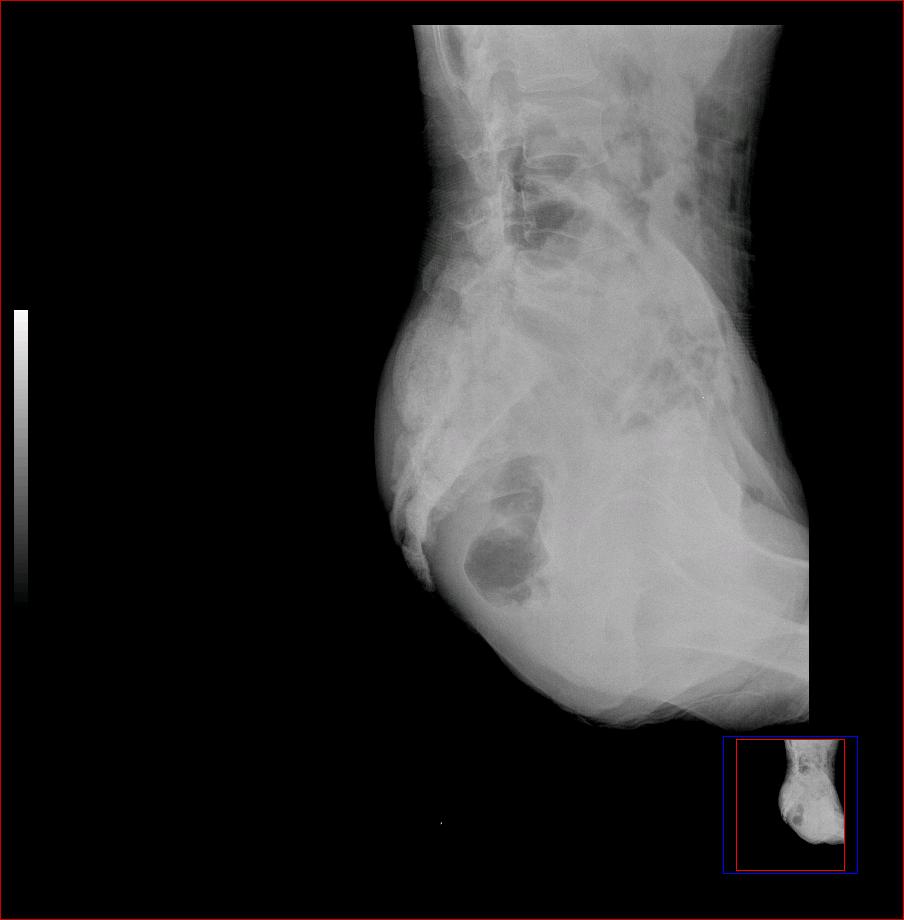

以下是引用ybing在2007-8-22 20:31:00的发言:[br]左侧髂骨溶骨样破坏;软组织肿块形成;其内未见肿瘤骨考虑纤维肉瘤或滑膜肉瘤不除外转移瘤

以下是引用qiushi在2007-8-22 21:39:00的发言:[br]双侧髂骨、骶骨侧快呈溶骨样骨质破坏,边缘模糊,左侧髂骨见骨折线,左侧髂部见软组织块影。考虑骨纤维肉瘤(中央型)伴病理性骨折,不排除骨髓瘤。建议本--周氏蛋白检查。[br] 鉴别点:[br] 骨纤维肉瘤,中央型者示边缘模糊的囊状溶骨破坏,一般无骨膜反映,可膨胀变形,突破骨皮质可形成软组织肿块,或并发病理性骨折。[br] 骨髓瘤,常表现为广泛的骨质疏松,皮质变薄或破坏,呈粟栗状、穿凿状、鼠咬状骨质破坏,边缘清晰,周围无硬化。[br] 骨转移瘤(溶骨型),表现为虫噬样、泡沫状圆形或卵圆形破坏区,很少出现软组织块影。[br][br][本贴已被 qiushi 于 2007-8-23 6:20:19 修改过]